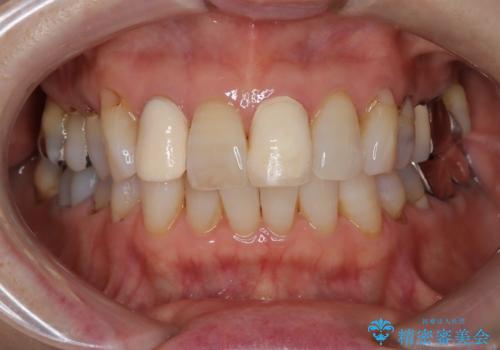

【外傷歯】根管治療から被せ物まで。

- 外傷により他院で治療中に転院を希望され受診されました。

前医では、抜歯も提案をされていましたが適切に治療を行うことで歯を保存することができました。

歯槽骨内水平性歯根破折は、抜歯の適応ではありません。